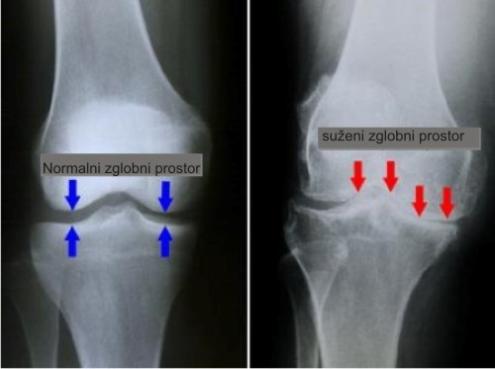

Uobičajeno znan kao artritis trošenja zgloba ( slika 1 ), OA je stanje kod kojeg je došlo do trošenja hrskavice između koštanih struktura u zglobu. Kada se taj proces razvije dolazi do struganja površine kostiju jedna od drugu uz smanjenu sposobnost apsorbiranja udaraca. To struganje uzrokuje pojavu boli, otečenost, ukočenost, ograničenu pokretljivost te ponekad i razvoj koštanih izdanaka OA koljena je najčešći oblik OA ( slika 2 ). Iako se može javiti kod mlađih ljudi, ipak rizik za razvoj istoga se povećava nakon 45.god života, s time da su žene sklonije razvoju.

Slika 2.